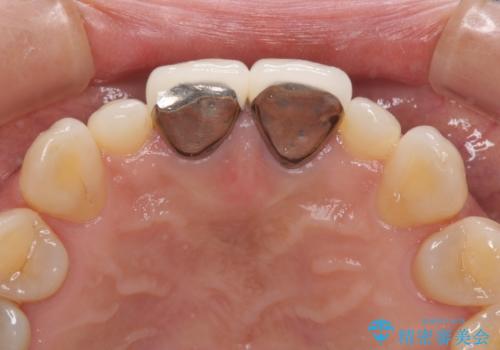

前歯をメタルフリーに 根管治療で不安を取り除いてから

- 他院で奥歯に虫歯があると言われて、ご来院された患者様です。チェックしたところ、奥歯に虫歯は認められませんでした。

前歯に違和感や根尖病巣(根の先に細菌が溜まっている)が認められたため、治療をご提案しました。

セラミック治療と根管治療を行いました。

患者様は、もともと奥歯の虫歯を心配してご来院されましたが、前歯に問題が見つかりました。

金属を使用したメタルボンドクラウンが入っていたため、いつかオールセラミックにしたいときに根管治療も行ったほうが良いとご提案し、今回行いました。